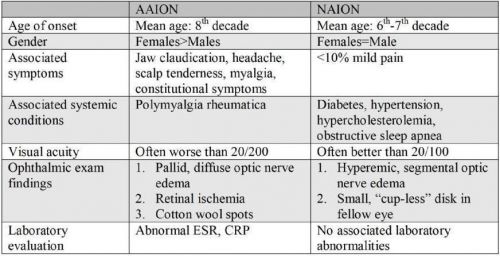

The most common disease in the differential diagnosis of GCA with decreased vision is NAION.

As shown in Table 1, NAION is associated with small-crowded optic nerves, hypertension, diabetes, and hyperlipidemia,[31] whereas AAION is not necessarily associated with the same vascular risk factors. In addition, patients with GCA are typically older than those with NAION (i.e. 8th–9th decade vs. 6th–7th decade). In NAION, patients will usually not note any associated systemic symptoms such as headache, jaw claudication, scalp tenderness, weight loss, anorexia, fever, or myalgias/arthralgias. In general, the vision loss from GCA is more severe than with NAION, with one third of patients with AAION demonstrating a visual acuity worse than 20/200; most patients with NAION retain a visual acuity near 20/80.[118] Patients with AAION may complain of preceding amaurosis fugax as well as other ocular symptoms including diplopia, fellow eye involvement, or ophthalmoplegia.

The physical examination also differs between these two diseases. Whereas AAION is associated with a diffuse “chalky” white edema, eventual cupping of the disc, and possible coexistent retinal ischemia, NAION often demonstrates segmental optic nerve edema with eventual sectoral or total flattening and pallor.[36][58] In addition, laboratory evaluations such as ESR and CRP are usually normal in patients with NAION.